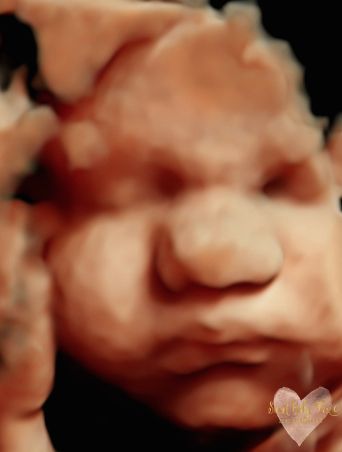

3D/4D/5D Ultrasound Gallery

Take a peek at our Photo Gallery. All of our 2D, 3D, 4D, HD elective ultrasound images are truly ours. They come directly off our machine from our highly trained staff. We can start getting great 3D/4D images as early as 10 weeks!